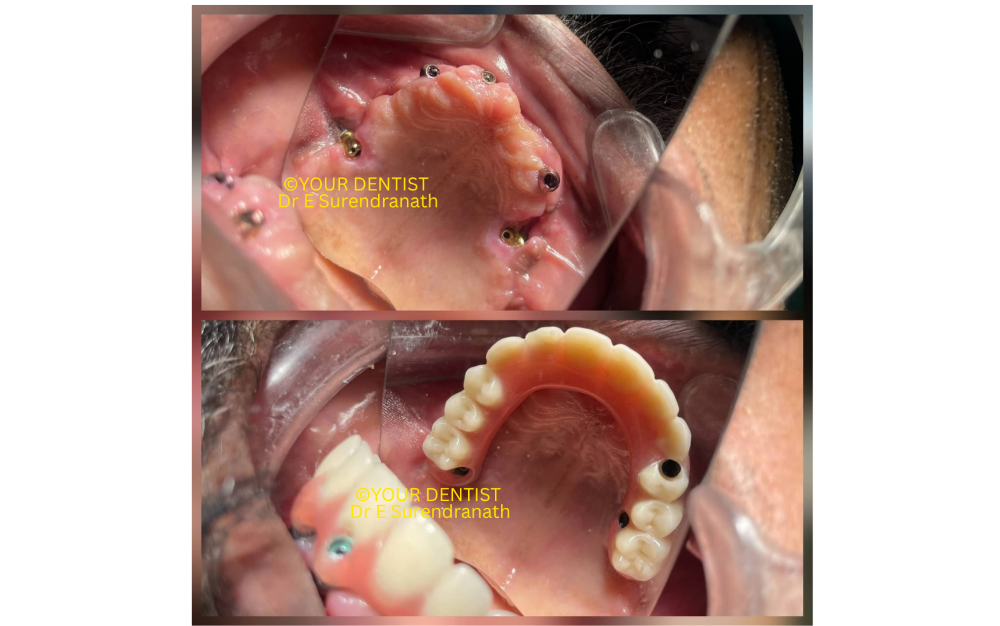

Because adequate primary stability was achieved, the implants were immediately brought into function with a fixed final restoration. The intraoral images clearly show the transition from implant abutments to the fixed prosthetic phase. Within a short span, the patient moved from severe dental compromise to a functional fixed-teeth situation. The intraoral images also show you that we have used multi-unit abutments for each and every case, and also these multi-unit abutments will make the prosthesis sit in a favorable position, unlike the normal abutments, which can’t be tamed into position easily, and also you are forced to give a cement-retained teeth set, but multi-unit abutments give you an option for screw-retained teeth sets.

The smile photographs demonstrate the clinical change very well. Before treatment, the patient had a compromised dental appearance and poor support. After treatment, the patient regained fixed teeth, smile support, and a far more confident smile as seen in fig 3.

Fig 3

Immediate loading full arch dental implant prosthesis